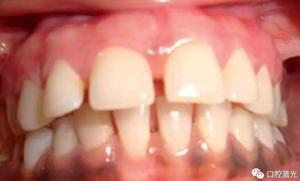

術(shù)后即刻

患者術(shù)后無明顯疼痛不適,沒有出現(xiàn)大量出血、感染或結(jié)痂現(xiàn)象。整個(gè)恢復(fù)過程較為順利?;颊呓邮芏雀撸委熜Ч黠@。